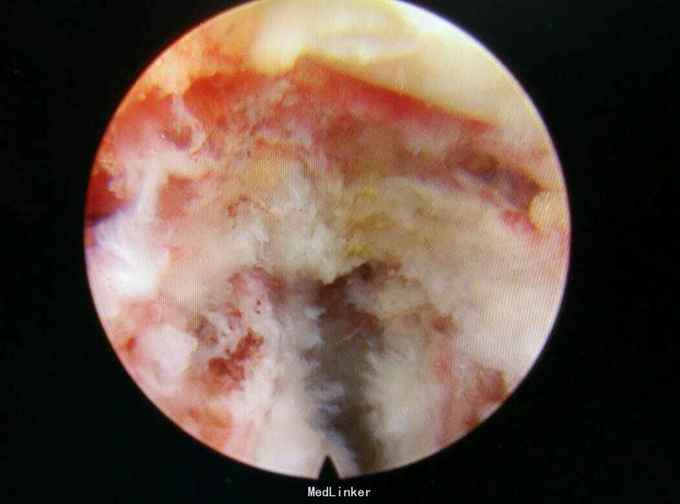

诊断:L45腰椎间盘脱出游离。 治疗:行侧路椎间孔镜手术。

术后症状缓解,左腿直腿抬高80度。此类患者,行侧路椎间孔镜有一定难度,但是侧路椎间孔镜创伤小,恢复快。各位大侠对这样的病例还有什么好的处理方案?